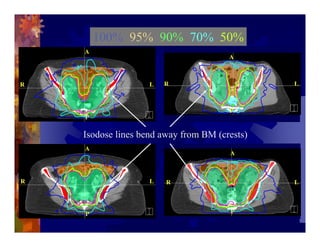

1) Intensity modulated radiation therapy (IMRT) is a technique that uses computer software to conform the radiation dose to the shape of the tumor, reducing dose to surrounding normal tissues and decreasing toxicity. 2) Numerous studies have shown IMRT provides better sparing of the small bowel, bladder, and rectum compared to conventional radiation for gynecologic cancers. 3) IMRT may allow dose escalation to high risk sites or involved nodes while maintaining normal tissue doses. Some studies have also investigated using IMRT as an alternative to brachytherapy boosts. 4) Clinical studies suggest IMRT results in low rates of acute gastrointestinal and genitourinary toxicity compared to conventional radiation for